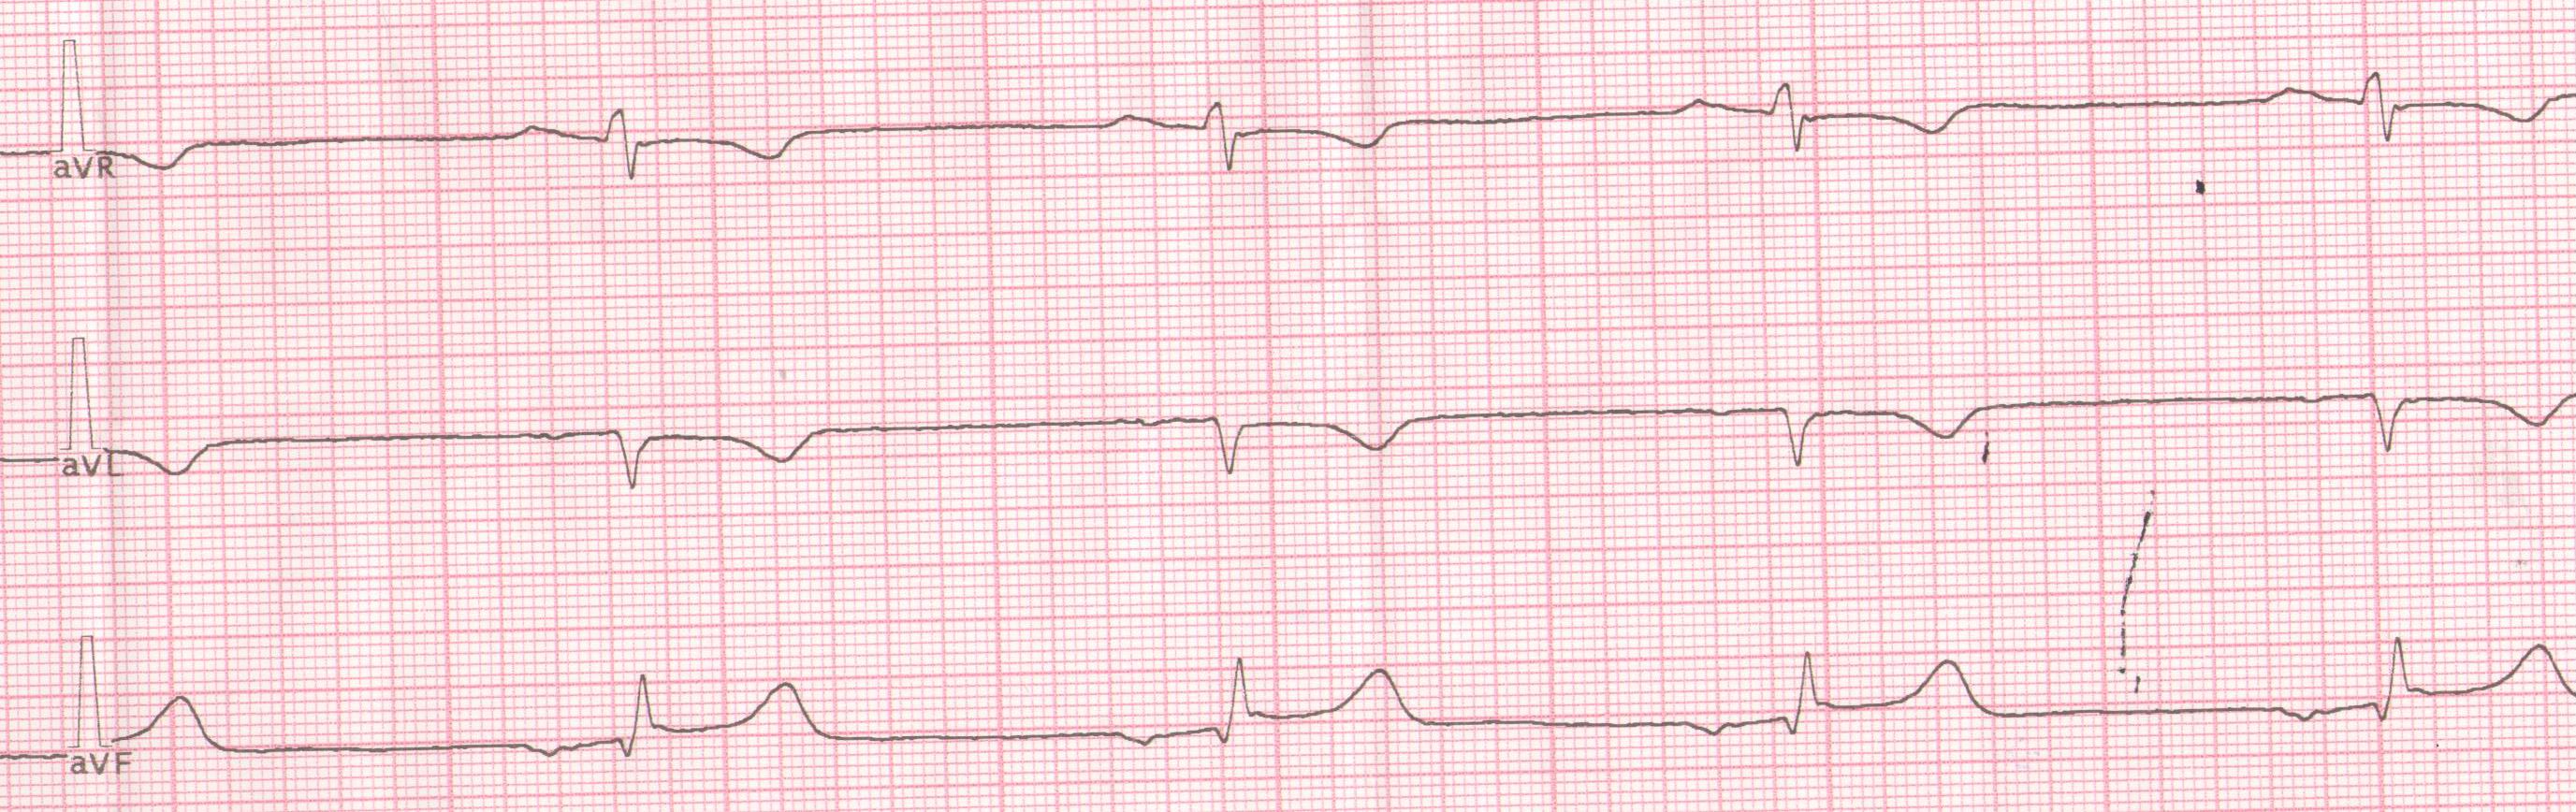

Заголовок сообщения: Декстракардия

Сначала ЭКГ записана как обычно, затем как надо